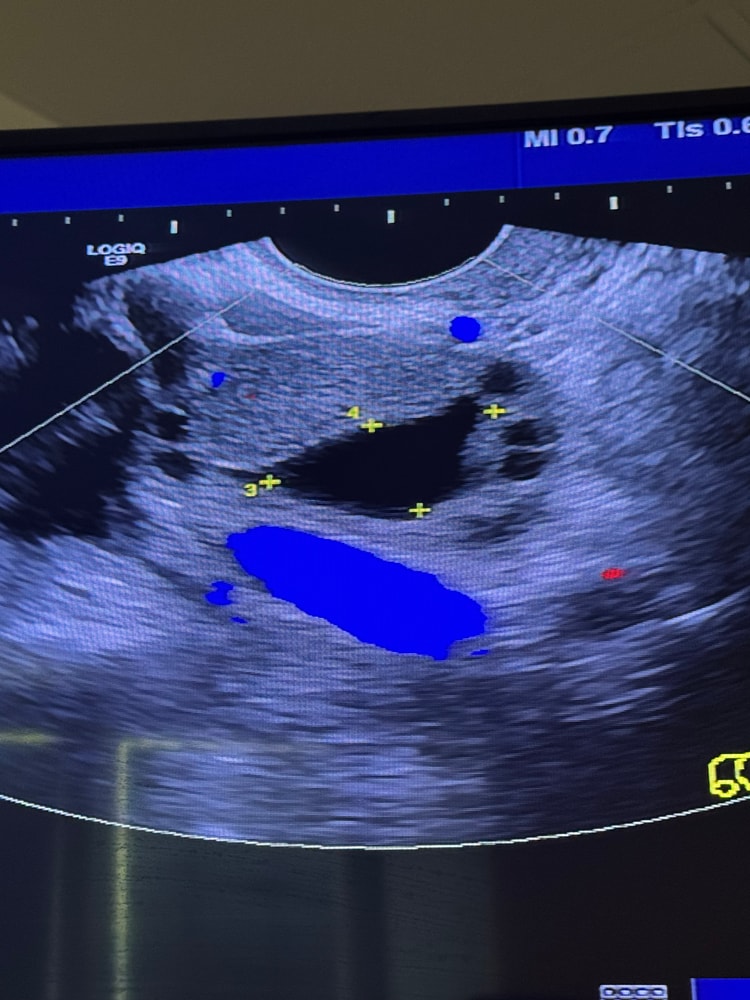

Видно перфузию ( кровоток ) вокруг образования

Размер образования около 2-3 см.

Перфузия характерна больше для желтого тела